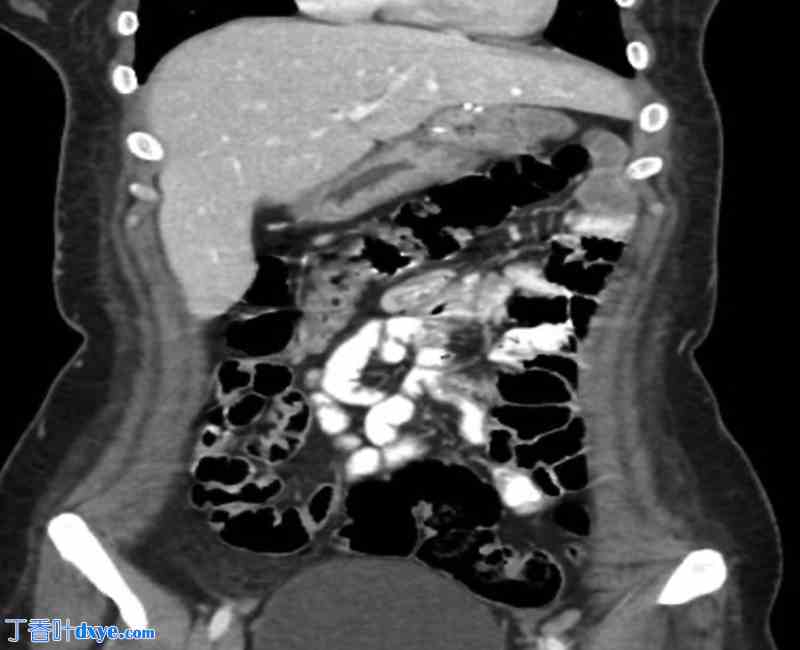

图 3

3.jpg

CT 图像显示肠系膜漩涡状结构和扩张的排除胃(病例 1)。